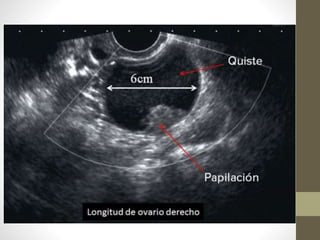

• ECO (TV)→ Ovario Poliquísticos Bilateral

• 12 o más Folículos en c/ovario de 2-9 mm de Diámetros

• Aumento del Volumen Total del Ovario (> 10 cm)

• Es característica esta imagen periférica en “collar de perlas”

• DATO: Volumen del Ovario → es la Suma del Diámetro Transverso +

Vertical + Oblicuo por 0,5